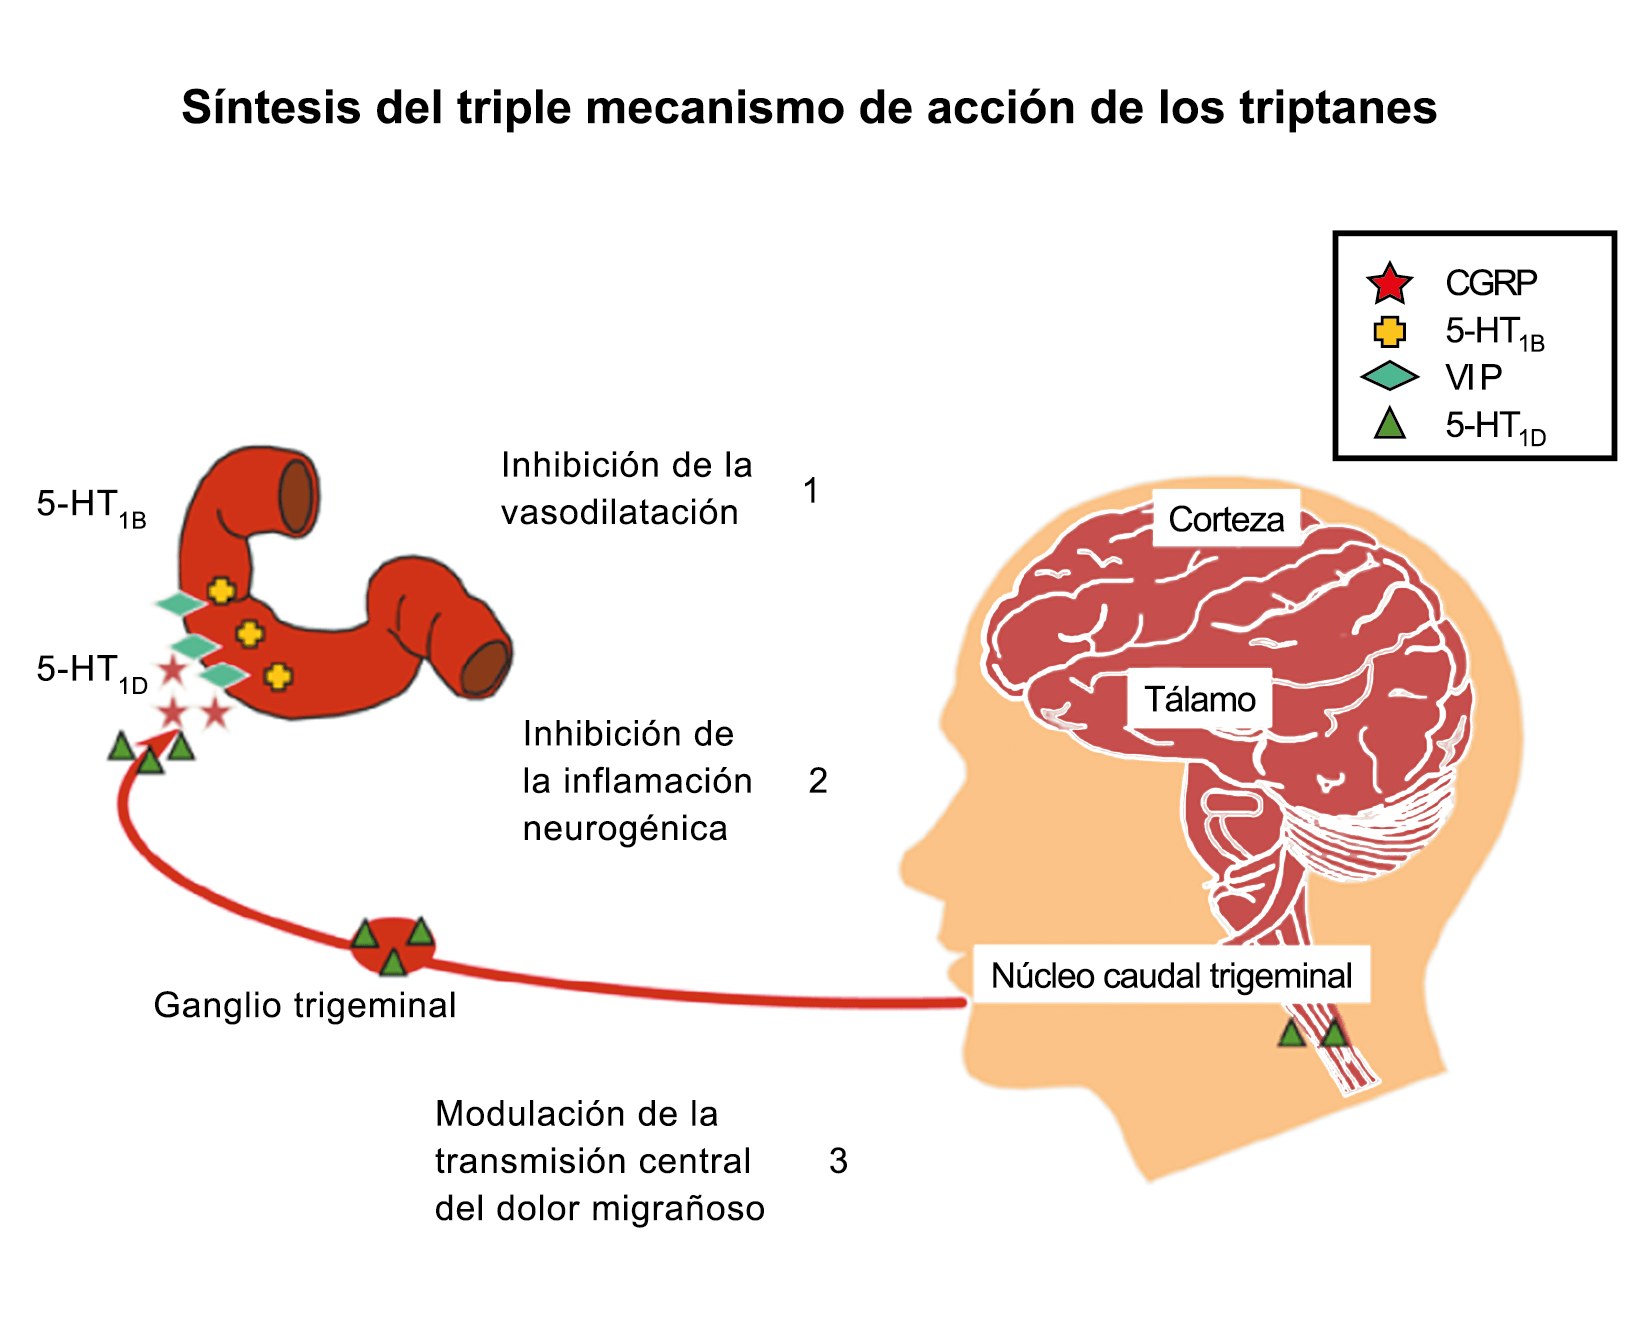

Posteriormente diversos estudios demostraron que la infusión de 5-HT podría abortar tanto la cefalea inducida por reserpina(55) como la espontánea(56). En respuesta a estos estudios, el sistema del receptor 5-HT ganó mucha atención, lo que culminó con el descubrimiento de los triptanos, la serotonina y los agonistas del receptor 5-HT1B/1D(57). Todos exceptuando el 5-HT3 (canal iónico controlado por ligando) son receptores acoplados a proteína G. Si bien los triptanos se clasifican como agonistas de los receptores 5-HT1B/1D, la mayoría también activa en menor medida los receptores 5-HT1A, 5-HT1E o 5-HT1F(58). Originalmente, los triptanos se desarrollaron para actuar sobre la vasculatura craneal, una idea apoyada por sus claras acciones vasoconstrictoras(59) (Figura 25) y la expresión preferencial del receptor 5-HT1B en los vasos craneales más que en los periféricos(60).

Un mecanismo neural de los triptanos en las terminaciones del nervio trigémino periférico podría inhibir la liberación de neuropéptidos proinflamatorios y la vasodilatación dural neurogénica(63), lo cual era consistente con el tema en desarrollo de la migraña como una enfermedad neurovascular. (Figuras 26 y 27)

En la figura 28 se muestra un resumen de los fármacos y sus mecanismos de acción en el contexto del sistema trigémino vascular.

A pesar de la clara farmacología de los triptanos en el tratamiento de la migraña, su uso es limitado en pacientes con factores de riesgo cardíaco(61), lo que obliga a dirigirse a receptores que carecen de acción vasoconstrictora. Una de esas dianas es el receptor 5-HT1F, que es activado hasta cierto punto por algunos triptanos, como el naratriptán y no por otros, como el rizatriptán(62). (Tabla 2)